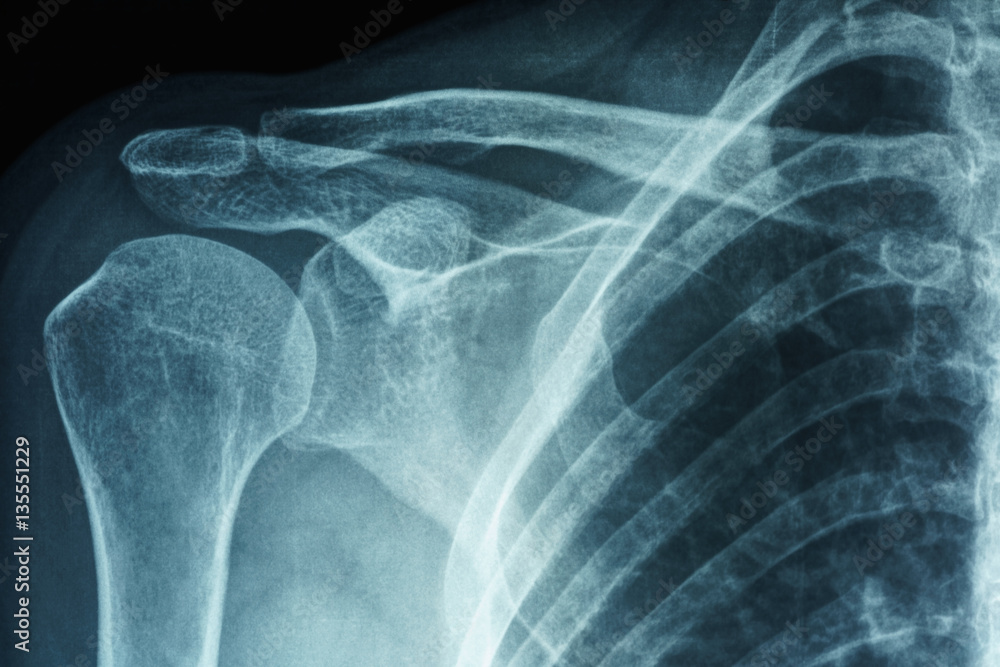

Adhesive Capsulitis Frozen Shoulder X Ray . The diagnosis is commonly made through a combination of clinical history and physical examination findings, but early signs of. Adhesive capsulitis, also known as “frozen shoulder,” is a common shoulder condition characterized by pain and decreased range of motion, especially in external rotation. Symptoms usually start slowly and get worse over time. Adhesive capsulitis or “frozen shoulder” is an inflammatory condition of the glenohumeral joint synovium and capsule leading to a restricted range of motion. Thick bands of tissue — called adhesions — develop. In many cases, there is less synovial fluid in the joint. In frozen shoulder, the shoulder capsule thickens and becomes stiff and tight. Adhesive capsulitis, also known as frozen shoulder, is an inflammatory condition characterized by shoulder stiffness, pain, and significant loss of passive range of. Frozen shoulder, also called adhesive capsulitis, is a condition involving pain and stiffness in your shoulder joint.

From stock.adobe.com

Xray film of primary frozen shoulder or adhesive capsulitis of Asian female patient Stock Photo Adhesive Capsulitis Frozen Shoulder X Ray Symptoms usually start slowly and get worse over time. Frozen shoulder, also called adhesive capsulitis, is a condition involving pain and stiffness in your shoulder joint. In many cases, there is less synovial fluid in the joint. In frozen shoulder, the shoulder capsule thickens and becomes stiff and tight. Adhesive capsulitis, also known as “frozen shoulder,” is a common shoulder. Adhesive Capsulitis Frozen Shoulder X Ray.